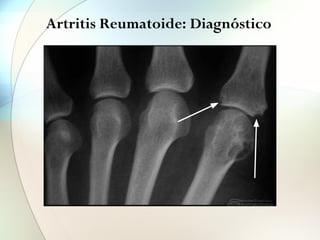

• Rx: Osteopenia yuxtarticular, pérdida cartílago

articular y erosiones óseas.

Artritis Reumatoide: Diagnóstico

Signo precoz:

Osteopenia yuxtaarticular